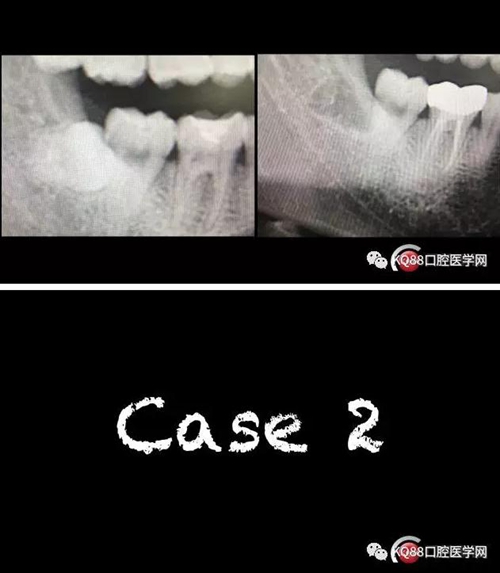

智齒拔除

此文關(guān)鍵字:智齒拔除